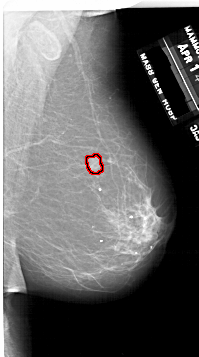

FILE: A_1747_1.RIGHT_CC.OVERLAY

TOTAL_ABNORMALITIES 1

ABNORMALITY 1

LESION_TYPE MASS SHAPE LOBULATED MARGINS ILL_DEFINED

ASSESSMENT 4

SUBTLETY 3

PATHOLOGY BENIGN

TOTAL_OUTLINES 1

BOUNDARY